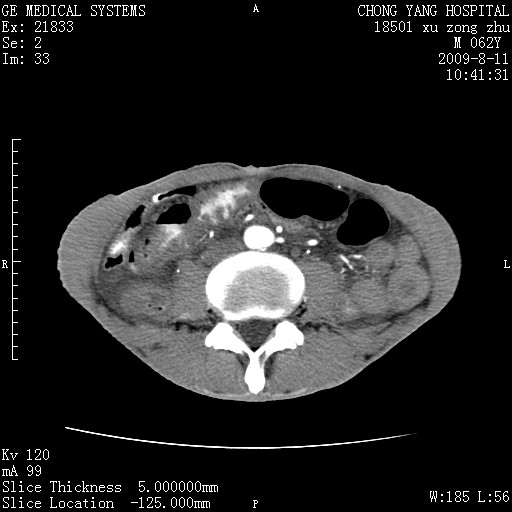

以下是引用杀毒软件在2009-8-11 16:35:00的发言:[br]肝内胆管扩张局限于左叶,胆管内有结石伴肝外胆管结石,胆管壁增厚呈弥漫性并发腹腔积液,胰腺边界模糊。[br][br]考虑---胆总管及肝内胆管结石继发胆管炎及胰腺炎,左肾下极囊肿,腹水。

以下是引用zjzjr在2009-8-11 17:35:00的发言:[br]肝内胆管扩张局限于左叶,胆管内有结石伴肝外胆管结石,胆管壁增厚呈弥漫性并发腹腔积液。[br][br]考虑---胆总管及肝内胆管结石继发胆管炎,左肾下极囊肿,腹水。